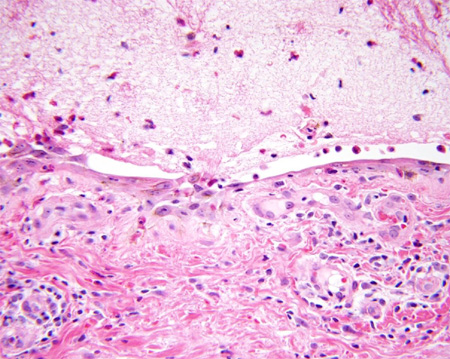

Буллезный пемфигоид

Результат световой микроскопии: субэпидермальный пузырь

Из коллекции д-ра Весны Петрон-Росик (Dr Vesna Petronic-Rosic)